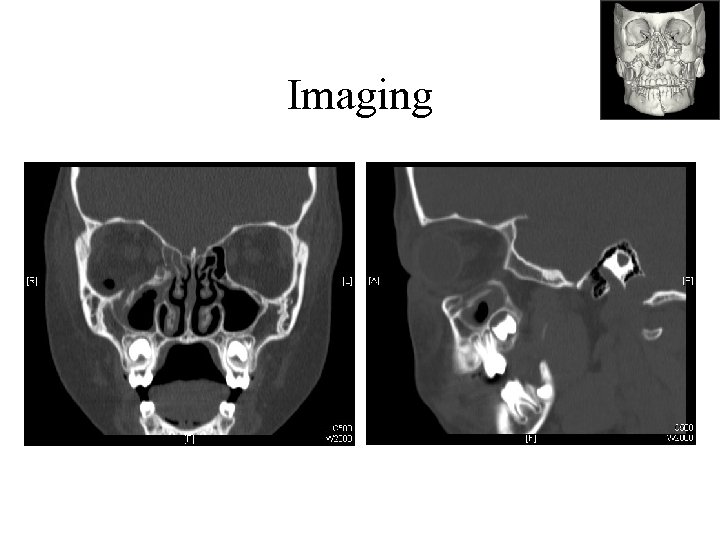

Imaging